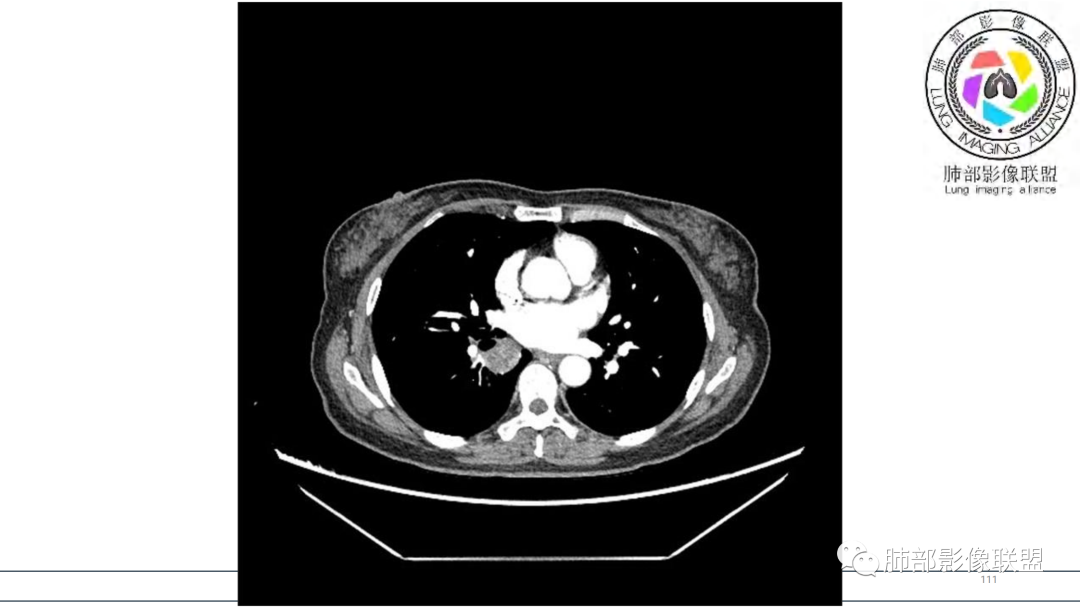

2.右肺下叶及中间段支气管后方类圆形块影,边界较清楚,未见分叶及毛刺,病灶部分突入支气管腔内(冰山一角),局部管腔狭窄,相应肺叶未见片影或体积变化。

3.块影密度均匀,未见液化坏死及钙化,渐进性强化,强化显著。

4.双肺门及纵隔未见增大淋巴结。未见胸腔积液。

中青年女性,支气管管腔内外肿块(“冰山征”),边界较清楚,强化显著,未见阻塞性肺不张,尽管未出现“类癌综合征”临床表现,仍然符合典型类癌影像学表现。

类癌临床表现无特异性,影像学检查仍然是肺类癌的主要诊断依据。其特征性表现是孤立的、边界清楚的肿物,密度可均匀或不均匀,边缘多清楚锐利,部分病例可见浅分叶及毛刺。类癌侵及的支气管局部增厚,与正常的管壁分界清楚,局部呈乳头状突起,表面光滑。肺门旁肿块往往边缘光整、轮廓清楚、密度均匀,增强扫描大多呈均匀明显强化,可有持续强化或延迟强化。中央型肺类癌可引起支气管壁局限性增厚,形成轮廓光滑的管壁结节,并与腔外大病灶形成“冰山征”。少数病例可沿支气管腔内长轴生长,呈指套样改变,类似肺鳞癌,但较肺鳞癌血供丰富。